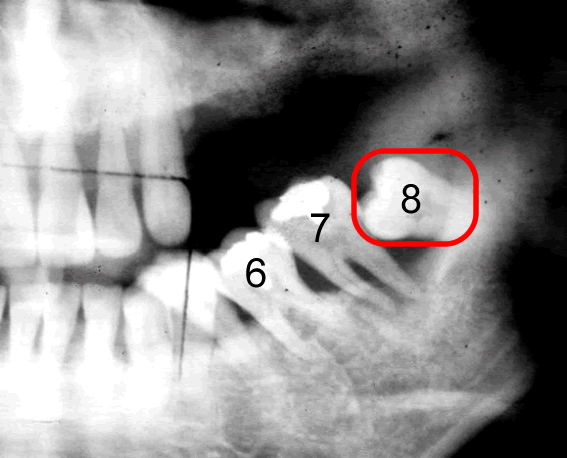

このレントゲン写真は40代の方です。

8番目が親知らずです。

横に向いて生えていますね。

親知らずの手前の歯7番目、その手前の歯6番目、どうなっているでしょう?

6番目は斜めに倒れて、かつ、上に上がっていますね。

親知らずに押し上げられているんですね。

このレントゲン写真でもう一つ重要なことが、あります。

それは、親知らずのすぐ手前の7番目の歯の根っこをご覧下さい。

歯を支えている骨が溶けているんです。

レントゲン写真というのは硬いところが白くうつります。

5番目の歯の根っこのあたりは歯の根の周りがまだもや~っと白くうつっています。

これは「骨」が写っているんです。

しかし、7番目には、骨が、ない。

さらに6番目の根っこの7番目よりのあたりまで骨が溶けています。

7番目の歯を支えている骨が全然ないのです。

6番目の歯を支えている骨が後ろ半分ないのです。

ということはこの7番目の歯はグラグラに揺れています。

抜かなければならないということです。

ほっといてもそのうち勝手に抜けます。

「親知らず」を抜かずに放置しておいたために、その「親知らず」が横に押し上に押し、さらにこの7番と8番の間に溜まったバイ菌が取りきれないわけです。